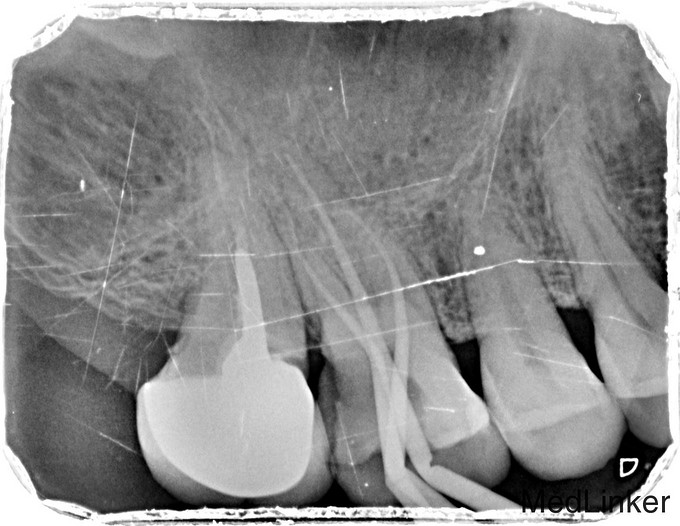

主诉:右上后牙食物嵌塞不适数日 现病史:数日来,患者右上后牙食物嵌塞疼痛不适影响进食来诊。 既往史:健康 过敏史:无

临床检查:16牙合面无明显的龋坏,远中邻面探(++),冷(++),叩(-),松动度(-),牙周红肿.牙石一度。 辅助检查:X线示16根尖周牙周膜增宽。远中邻面部分吸收。

诊断:16慢性牙髓炎 治疗:16局麻降牙合,开髓拔髓寻找根管口,建立直线通路,扩通根管,确定工作长度。S3/EDTA凝胶镍钛器械,低浓度次氯酸钠冲洗根管,预备至25/06,氢氧化钙诊间封药,牙周洁治,抗炎治疗 ,一周后复诊,试主尖X线示恰充,试干根管,导AH-PLUS糊剂,VDW热压胶垂直加压根充,术后见根管恰充,暂封观察择期桩冠修复。